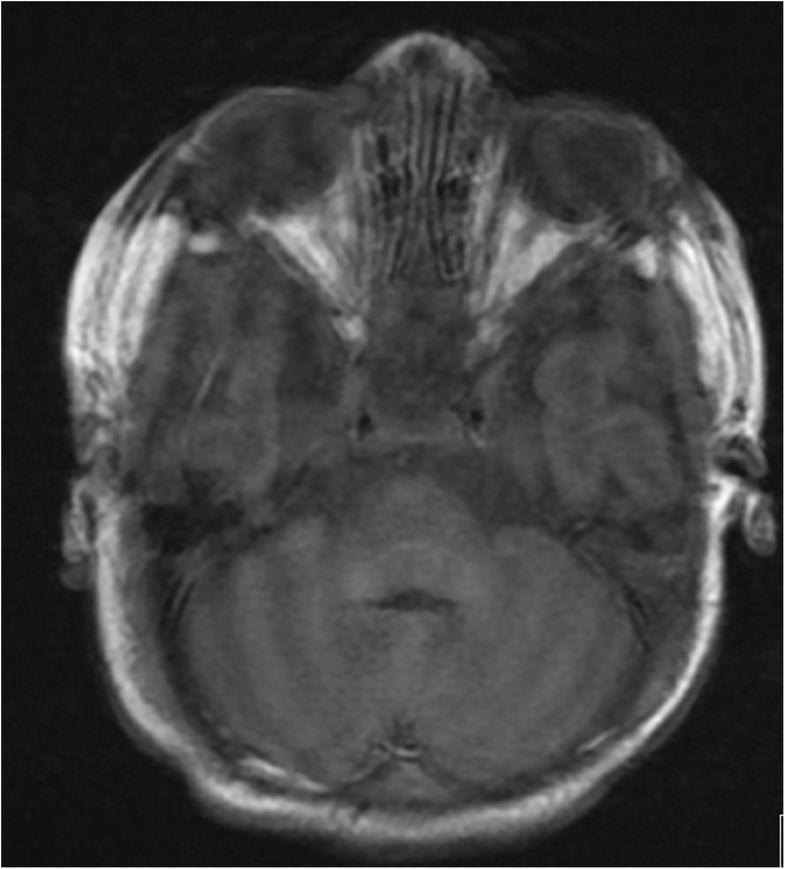

(PDF) Vitamin K deficiency bleeding presenting as impending brain How Common Is Vitamin K Deficiency Bleeding Frequently asked questions about vitamin k deficiency bleeding. Protect your baby from bleeds. If left untreated in adults, vitamin k deficiency can result in excessive bleeding and become dangerous. Learn more about how vitamin k deficiency bleeding develops, its common causes and symptoms, and how a doctor might treat. What is vitamin k, and how do low levels of vitamin. How Common Is Vitamin K Deficiency Bleeding.